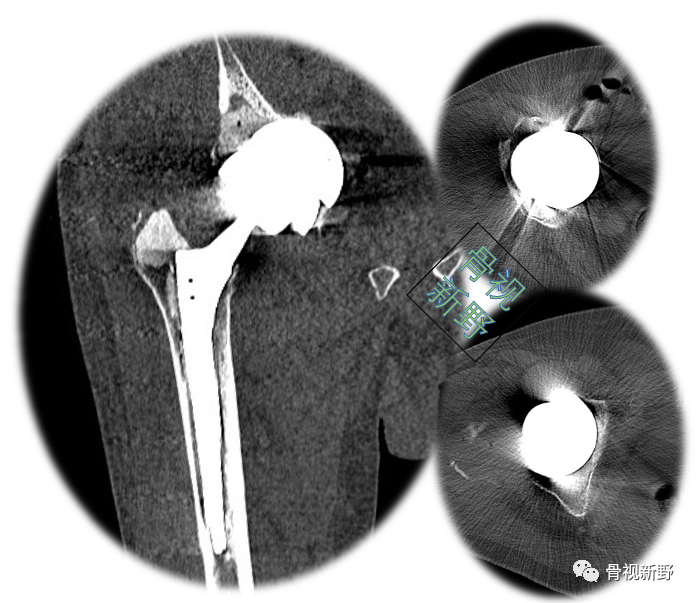

完善术前常规检查后,择期行翻修术:髋臼侧以cup-in-cup技术翻修;股骨侧以水泥柄翻修。

术后X光片

术后CT